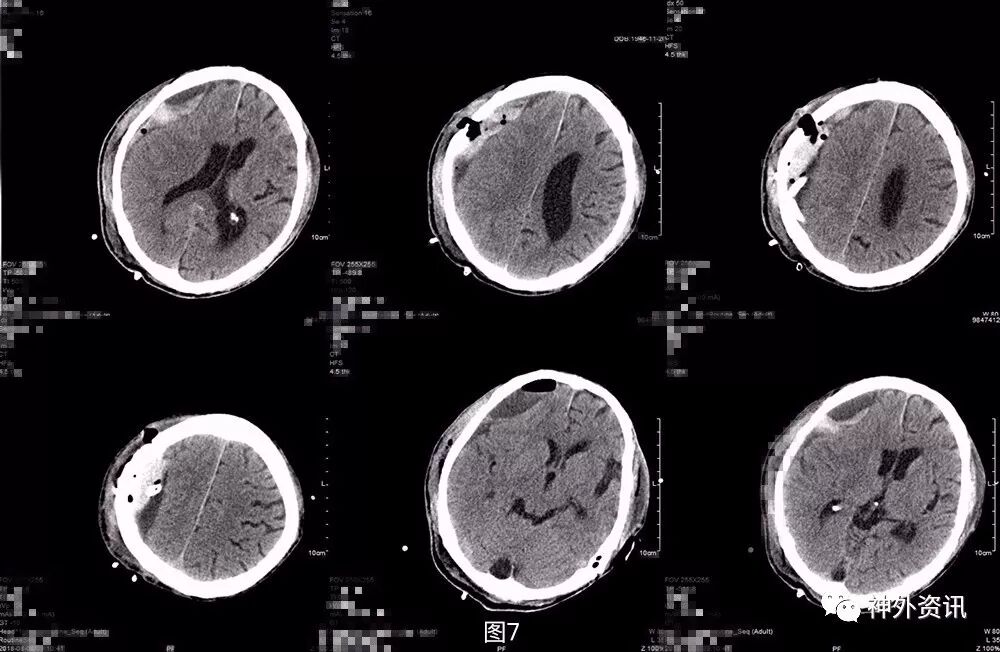

第三次术后第5天再次复查头颅CT,显示局部积气比前片吸收,但积血积液仍较明显(图9)。考虑患者神志及肢体肌力基本同前,继续予以药物保守治疗。之后患者逐渐神志转清,左侧肢体肌力好转至3-4级,期间复查头颅CT(图10)提示局部积血密度逐渐下降,提示血肿液化可能,于术后半月稳定后转康复治疗,定期复查头颅CT。

图9. 第三次术后第5天头颅CT,显示局部积气比前片吸收,但积血积液仍较明显。